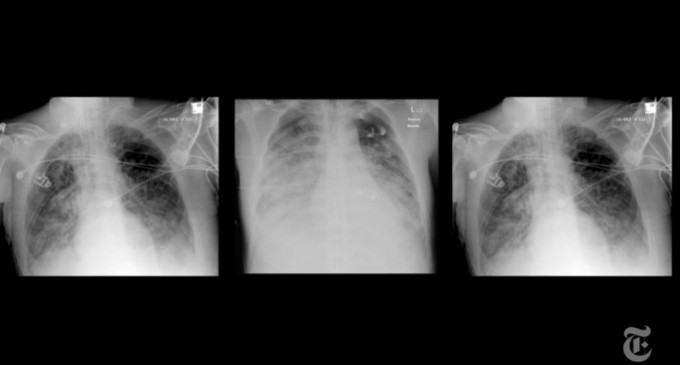

Pacienta provine din regiunea de vest Kansai și s-a îmbolnăvit de Covid-19 anul trecut, fiind ținută luni de zile conectată la un ventilator artificial. Infecția a lăsat leziuni atâtâ de severe încât plămânii ei nu mai erau funcționali astfel încât nu ar fi supraviețuit în absența transplantului.

Potrivit studiilor de specialitate, plămânii celor care au fost infectați cu covid pot prezenta leziuni luni de zile după recuperare.